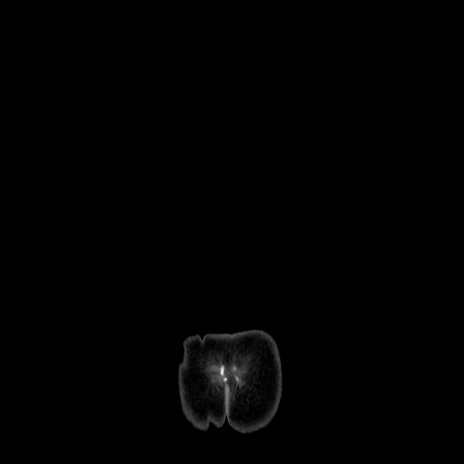

MRI(4日後)